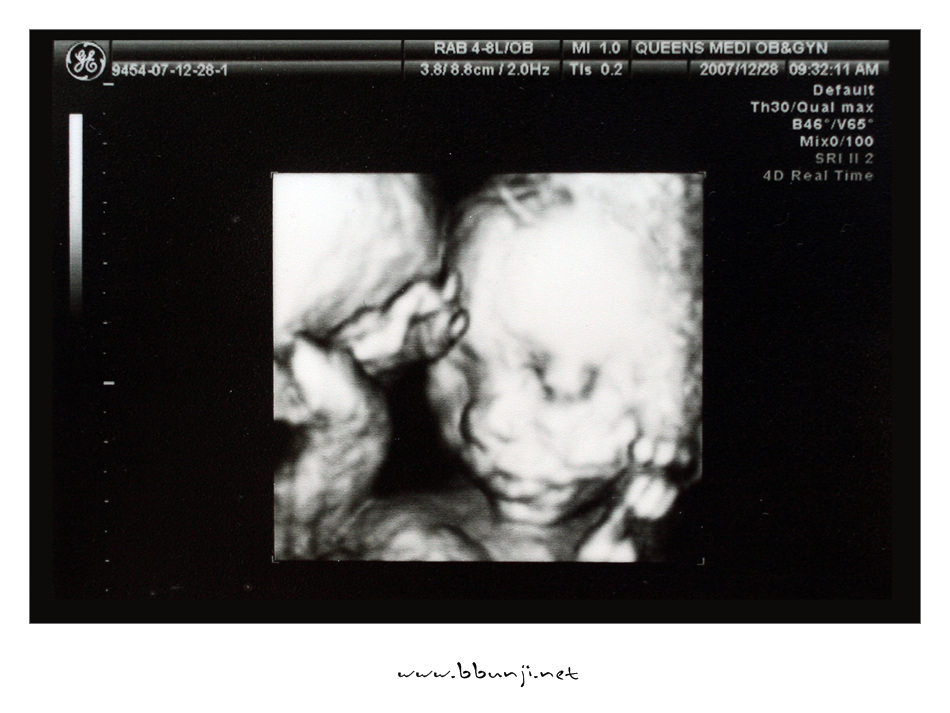

드디어 우리 사랑이 얼굴 공개…

병원에서 정밀초음파를 했는데 우리 사랑이 얼굴이 잡혔네요.

손으로 얼굴을 가리고 있어서 지은이가 물 두컵 마시고 계단을 7층까지 오르락 내리락 두번이나 했습니다.ㅋㅋ

이쁘게 생겼죠..^^

아직 살이 덜 붙어서 좀 마른 얼굴이라고 하네요.